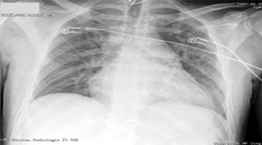

Ακτινογραφία

• Κάταγμα 4ης πλευράς αριστερά, λοιπά κφ

• Δίχως παθολογικά ευρήματα

• Κάταγμα 3ης πλευράς αριστερά, λοιπά κφ

• Αυξημένος καρδιοθωρακικός δείκτης